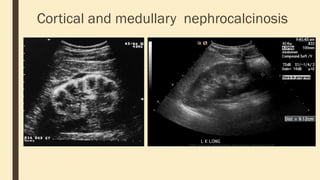

Cortical and medullary nephrocalcinosis

Medullary sponge kidney ■is a sporadic condition where the medullary and papillary portions of the collecting ducts are dysplastic and dilated and in most cases develop medullary nephrocalcinosis ■ Radiographic features ■ Medullary nephrocalcinosis occurs in the majority of cases (~80%). It may be unilateral or bilateral and affect a single or multiple pyramids. ■ Plain radiograph / CT ■ Clusters of pyramidal medullary calcification are characteristic. On IVP, the pyelogram may give a characteristic bouquet of flowers appearance or paintbrush appearance. ■ Ultrasound ■ Ultrasound of the kidneys of patients with medullary sponge kidneys typically demonstrates echogenic medullary pyramids. This appearance is found whether or not medullary nephrocalcinosis is also present. ■

Cortical and medullarynephrocalcinosis